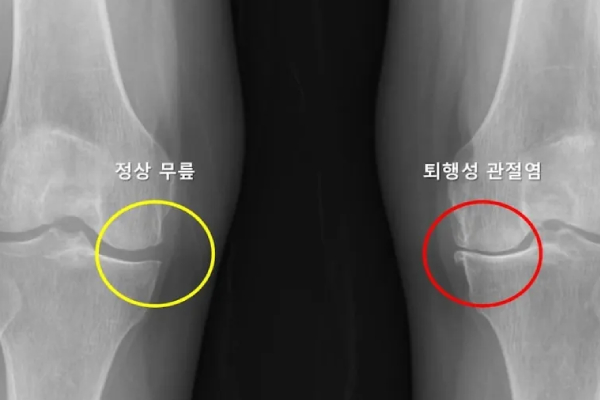

Исследователи из университетской больницы Сеульского национального университета разработали модель на основе искусственного интеллекта, которая позволяет спрогнозировать вероятность развития остеоартрита второго коленного сустава у пациентов с односторонним остеоартритом.

Наиболее значимым открытием в данном исследовании стало нахождение связи между степенью сужения суставной щели второго коленного сустава и риском развития остеоартрита: риск возрастает в 4,5 раза.

Также это первое исследование, в ходе которого обнаружилась значительная корреляция тяжести артрита, болевых ощущений и ограниченности движения при артрите коленного сустава и риска развития остеоартрита второго коленного сустава. Кроме того, точность модели при выявлении пациентов с высоким риском развития артрита коленного сустава составила 69 %.